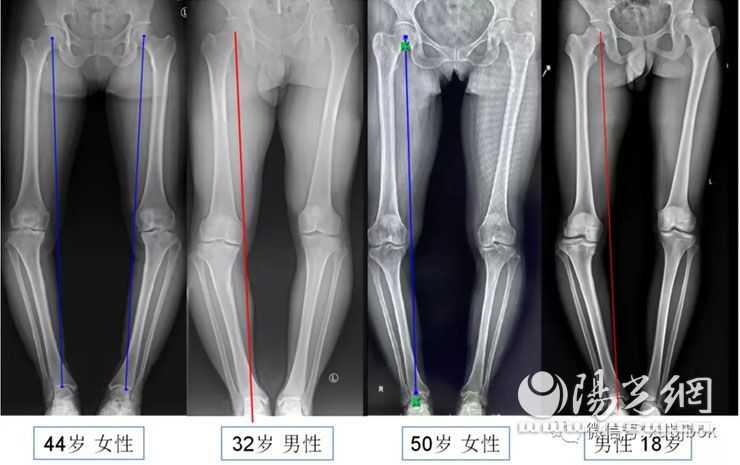

治疗膝关节炎的目的有两个,第一:缓解症状,就是让患者不疼,第二:延缓疾病的发展。对于65岁以上的老年人来讲,治疗主要就是缓解疼痛,也就是只要不疼就可以了,先吃药打针理疗,如果保守治疗无效,先考虑能不能用微创单髁治疗,如果还不行,那就根据全身情况决定了,身体好,那就换关节,如果全身情况差,那就只能采取保守治疗;但对于相对年轻的患者,临床治疗既要考虑缓解症状,让她不疼,还得考虑10年、20年甚至30年以后的事情,所以需要根据个体情况来选择最适合患者的治疗办法,如果有罗圈腿畸形、那么采用打针、口服药物、物理疗法等保守疗法可以缓解疼痛症状,但不能阻止关节炎快速进展,所以更得重视。虽然都是内翻膝,就是我们说的罗圈腿,但治疗方式也完全不同,需要根据年龄、关节磨损情况、畸形大小,畸形部位等综合考虑。

约有50%的膝关节炎患者,疼痛只局限于前内侧或内侧,往往伴有罗圈腿畸形,称之为膝关节前内侧关节炎,多数可以通过微创保膝疗法治疗。临床应用比较多的保膝疗法是单髁置换术(UKA)和胫骨高位截骨术(HTO)。这些目前都是非常成熟的手术,效果很肯定,对于畸形特别严重的,即使没有症状,也得尽早纠正,避免关节负重不平衡,造成关节过早的磨损。

第二种保膝方法是截骨术,主要针对65岁以下、相对年轻,疼痛主要在膝关节内侧,往往伴有罗圈腿畸形的患者,截骨术既能解决疼痛问题,而且对于年轻患者来讲,避免或者延迟换关节,术后还可以从事重体力和剧烈活动。

另外,对于“O型腿”、“X型腿”等有明显肢体畸形的青少年畸形,由于下肢负重不平衡,会导致膝关节过早的磨损,即使没有症状,也需要早期干预,防患于未然。